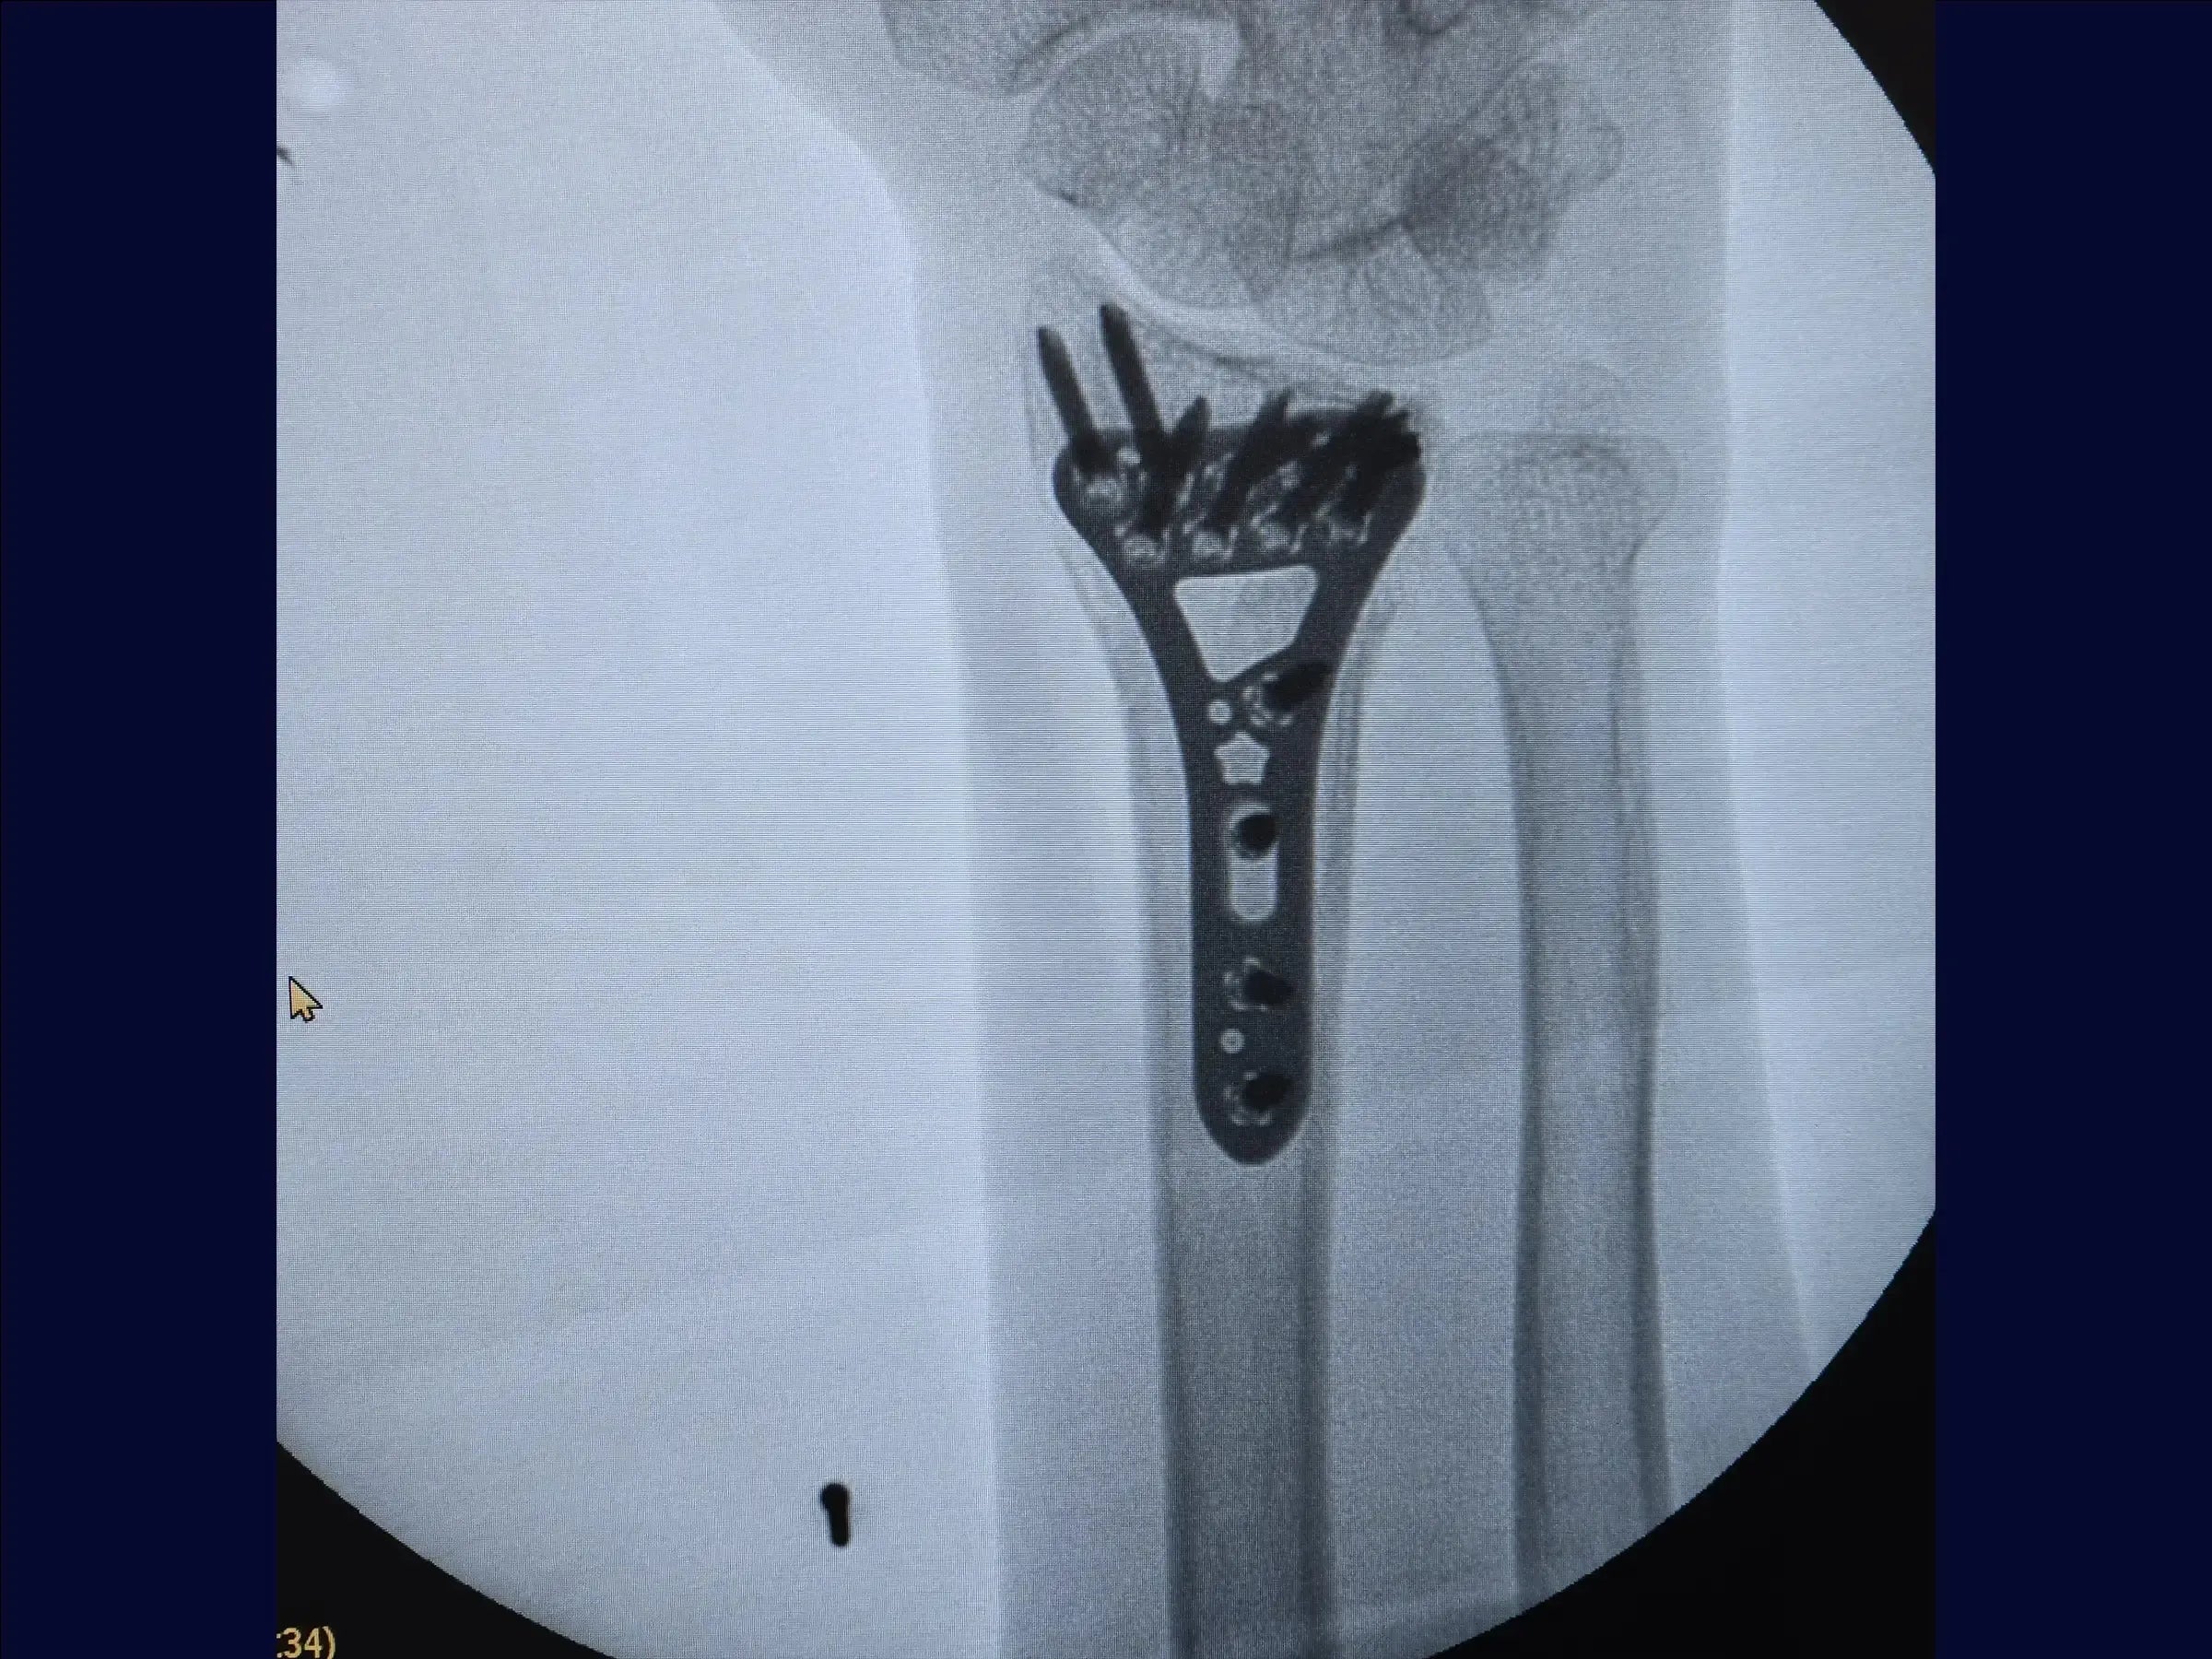

Fractura multifragmentaria del radio distal (abordaje volar)

Domine el tratamiento quirúrgico de las fracturas multifragmentarias del tercio distal del radio con esta formación centrada en el abordaje volar. El procedimiento busca restaurar la longitud radial y la congruencia articular mediante una combinación de tracción manual, fijación percutánea provisional y una estrategia de fijación con placa volar y tornillos de diferentes longitudes para estabilizar los múltiples fragmentos, incluido el componente dorsal, sin necesidad de un abordaje dorsal adicional.

- Preparación y fijación volar: Se reemplaza el retractor, se limpian los vértices de la fractura y se inserta la placa, respetando el límite articular. Se comienza con un tornillo cortical en el orificio oval para compresión. Se utilizan tornillos cortos para fijar el fragmento volar y, con maniobras digitales, tornillos largos estabilizan la superficie dorsal sin necesidad de otro acceso. Los tornillos cortos se reemplazan por tornillos largos (18-20 mm), incluyendo la estiloides, completando la osteosíntesis en los orificios restantes.

- Cierre y resultados finales: Se sutura el pronador cuadrado en línea recta. La reducción es satisfactoria, con una anatomía del radio prácticamente normal. Se realiza un cierre cutáneo para obtener un resultado satisfactorio.